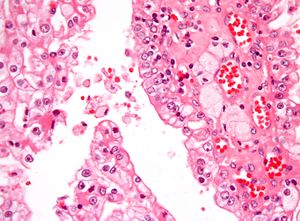

| Micrograph showing the most common type of kidney cancer (clear cell renal cell carcinoma). H&E stain. | |

The most common type of kidney malignancy is renal cell carcinoma,[11] which is thought to originate from cells in the proximal convoluted tubule of the nephron.[9][12] Another type of kidney cancer although less common, is transitional cell cancer (TCC) or urothelial carcinoma of the renal pelvis.[13] The renal pelvis is the part of the kidney that collects urine and drains it into a tube called the ureter.[13] The cells that line the renal pelvis are called transitional cells, and are also sometimes called urothelial cells. The transitional/urothelial cells in the renal pelvis are the same type of cells that line the ureter and bladder. For this reason TCC of the renal pelvis is distinct from RCC and is thought to behave more like bladder cancer.[13] Other rare types of kidney cancers that can arise from the urothelial cells of the renal pelvis are squamous cell carcinoma and adenocarcinoma.[9]

Renal cell carcinoma has been further divided into sub-types based on histological features and genetic abnormalities. The 2004 WHO Classification of the Renal Tumors of the Adults describes these categories:[17]

- Clear cell RCC